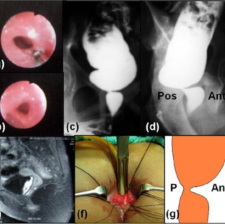

Fistulas

A fistula is an abnormal connection between two body parts, such as an organ or blood vessel and another structure. Fistulas are usually the result of an injury or surgery.Fistulas can occur throughout your body, either between different organs or from

Complex Fistulas

Complex fistulas include those that involve more than 30% of the external sphincter, fistulas with multiple tracts, recurrent fistulas, and those associated with other predisposing factors, including Crohn disease and radiation treatment.

Recurrent Fistulas

As aforementioned, recurrence of anal fistula may be attributed to poor postoperative care after surgery. Hence, regular follow-up with careful office examination is required to ensure proper healing of the surgical wound and detect early recurrence.

Horse Shoe Fistulas

Horseshoe fistulas are deep posterior anal fistulas which extend into the ischiorectal space with either unilateral or bilateral extensions in the shape of a horseshoe.